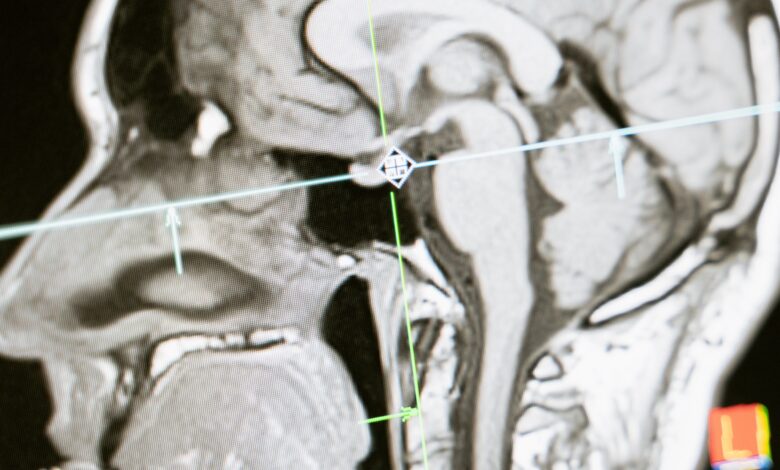

فقد فجرت دراسة حديثة مفاجأة بعدما كشفت أن الكوليسترول من النوع الجيد يمكن أن يكون له مخاطر صحية أخرى، ويرتبط بزيادة خطر الإصابة بالخرف لدى كبار السن.

وحذرت الدراسة التي نشرت في مجلة “لانسيت” العلمية أن حتى “الجيد” وهو مهم لصحة القلب والأوعية الدموية يرفع خطر الخرف لمن تزيد أعمارهم عن 75 عاما، وذلك بنسبة 42%.

ونتائج الدراسة هذه قد تدفع إلى البحث أكثر لفهم تأثيره على صحة الدماغ.